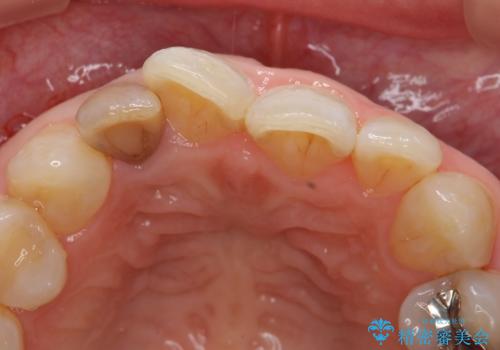

- 右上2番目の歯の変色が気になるといらっしゃった方の症例です。

再根管治療終了後、オールセラミッククラウンによる補綴を行いました。